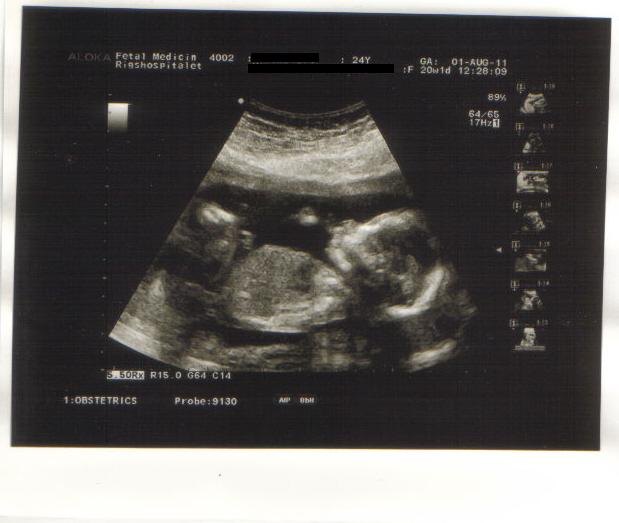

Så har vi fået MD scanningen overstået og alt var helt perfekt med mini mosleren

Den havde den rette størrelse og alt var bare HELT perfekt

Det er en aktiv lille basse og den var ikke særlig samarbejdsvillig, så hun måtte skubbe noget til ham for at kunne måle ham ordenligt, men det lykkedes.

Og I skal da ikke snydes for et billede af vores lille basse

Vedhæftede fotos (klik for at se i fuld størrelse)